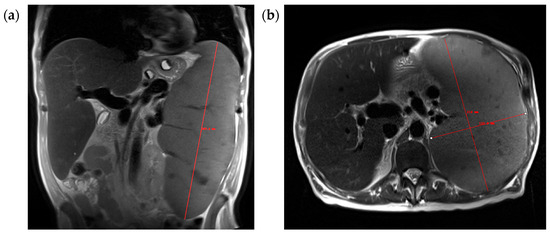

2.4. Spleen Volume Measurements

3.2. Coefficients of Variation and ICC: Ellipsoidal vs. Manual vs. Model Only vs. Model-Assisted